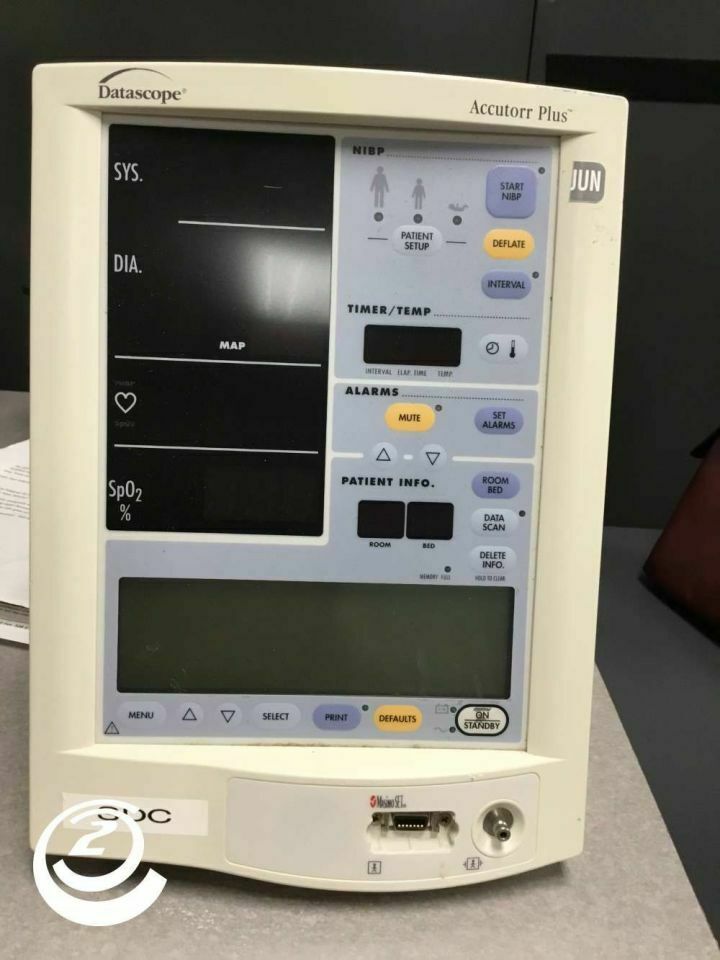

Save $ 15.15

DIAGNOSTIC ULTRASOUND MACHINES FOR SALE

DataScope Accutor Plus Modèle Moniteur 510DM Modèle 0998-00-0444-J71

Sale price$ 68.97

Regular price$ 84.12